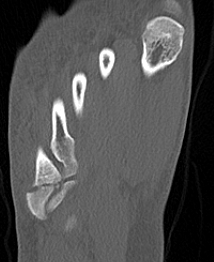

Xray

Zone 2 fractures

Union of zone 2 fracture with nonoperative care

Progression to nonunion of zone 2 fracture with nonoperative care